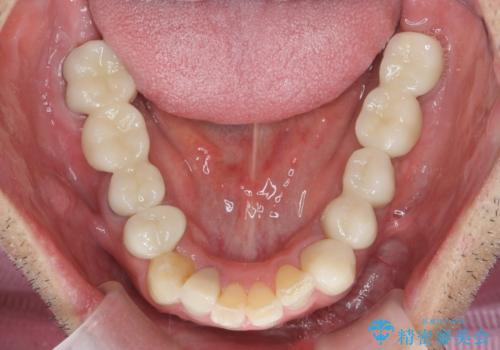

- 40代男性

- 「少しずつ色々な箇所が悪くなり、歯医者に通い続けている。全ての歯を長持ちするような状態にできるような治療を受けたい。」、と全顎・総合的な治療を希望され来院されました。

根管治療・矯正治療・歯周外科・セラミック補綴を含む様々な治療オプションを駆使し、長期間良好な状態に保てるような治療計画を立案します。

矯正治療を絡めた総合的な治療をお行なったことで、理想的な咬合関係を確立し安定した噛み合わせで仕上げることができました。

また歯周外科を行うことで歯ぐきの腫れを改善し、清掃性を高めています。